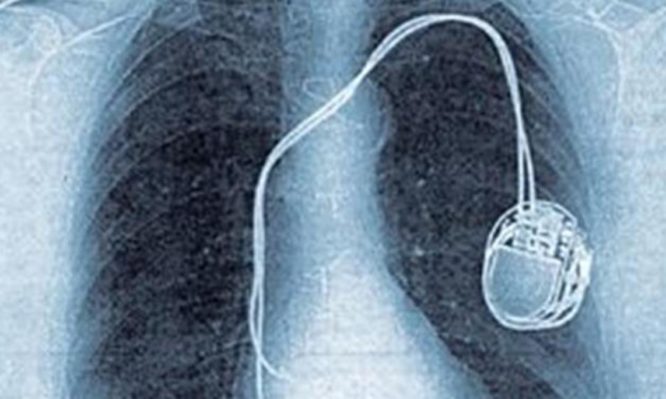

Ελλείψεις και σε βηματοδότες στα δημόσια νοσοκομεία

Στο «Τζάνειο» νοσοκομείο Πειραιά έχουν σε εκκρεμότητα αντικαταστάσεις βηματοδοτών από τον περασμένο Νοέμβριο δεδομένων των πολύ χαμηλών του Παρατηρητηρίου που δεν συμφέρουν το σύνολο σχεδόν των εταιριών οι οποίες προμηθεύουν αυτά τα υλικά…

Αυτό που έχει συμβεί, είναι ότι σε μεμονωμένο διαγωνισμό που έκανε το ΠΑΓΝΗ (Ηράκλειο Κρήτης) βρέθηκε τελικά μια προμηθεύτρια εταιρεία που έδωσε βηματοδότες σε εξευτελιστική τιμή και έκτοτε η τιμή αυτή μπήκε ως τιμή αναφοράς στο Παρατηρητήριο Τιμών και δεν αλλάζει… Στο ΠΑΓΝΗ όμως, μην ξεχνάμε ότι δραστηριοποιείται ο παγκοσμίου φήμης και σεβασμού καθηγητής Καρδιολογίας Παναγιώτης Βάρδας, που έχει διατελέσει και πρόεδρος της Ευρωπαϊκής Καρδιολογικής Εταιρείας, και είναι πολύ πιθανό -χωρίς να είμαστε απόλυτα σίγουροι γι΄αυτό- ότι για χάρη του και από σεβασμό στο πρόσωπό του δόθηκαν τόσο φθηνά οι βηματοδότες. Αυτό δεν σημαίνει ότι η ίδια ή άλλες εταιρίες μπορούν να πωλούν συνεχώς στην ίδια τιμή τα προϊόντα τους σε όλα τα νοσοκομεία της χώρας…

Το iatropedia είχε αναδείξει το θέμα και τον περασμένο Δεκέμβριο όταν αποκάλυψε τις ελλείψεις σε βηματοδότες και στο Κοργιαλένειο -Μπενάκειο (Ερυθρός). Το θέμα αυτό μπορείτε να το διαβάσετε εδώ.

Πάντως διαγωνισμοί έχουν προγραμματιστεί για το επόμενο διάστημα αλλά είναι μεμονωμένοι, όπως αυτός στο «Τζάνειο», και δεν αναμένεται να έχουν και πολύ καλή …τύχη. Κάτι πρέπει να γίνει αδιαμφισβήτητα με το Παρατηρητήριο Τιμών.